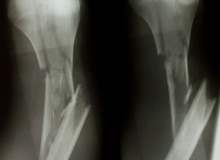

Fiziksel İstismar

Fiziksel istismar, bedensel yaralanma, ağrı ya da sakatlıkla sonuçlanacak fiziksel güç ya da şiddet uygulamaktır. Saldırı, darp ve uygunsuz yasaklamaları ve engellemeleri içerir.